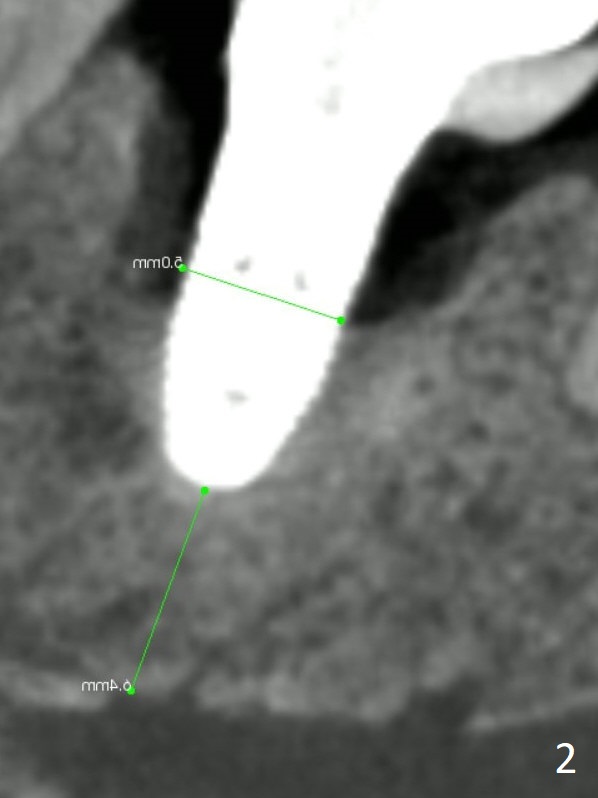

A 53-year-old woman has buccal gingival erythema and edema with deep pocket and purulent discharge. PA and CBCT show that the implant was placed distal and not deep enough (Fig.1,2) as well as buccal (Fig.3). When the failed implant is removed, try to place an implant mesiolinguoapically. Make purchase point/trough mesiolingual to the failed implant. Take PA with pilot drill for trajectory confirmation (Fig.1 red line). The implant will be 4 or 4.5 mm in diameter and 4 mm in the native apical bone. Use 1.6 and 3.8x11 mm Magic Drill until the lingual crest. Place PRF over the bone graft, Cyotplast buccally and provisional. Lower Molar Immediate Implant, Prevent Molar Periimplantitis (Protocols, Table), Armaments, #19 Xin Wei, DDS, PhD, MS 1st edition 12/10/2017, last revision 09/15/2020